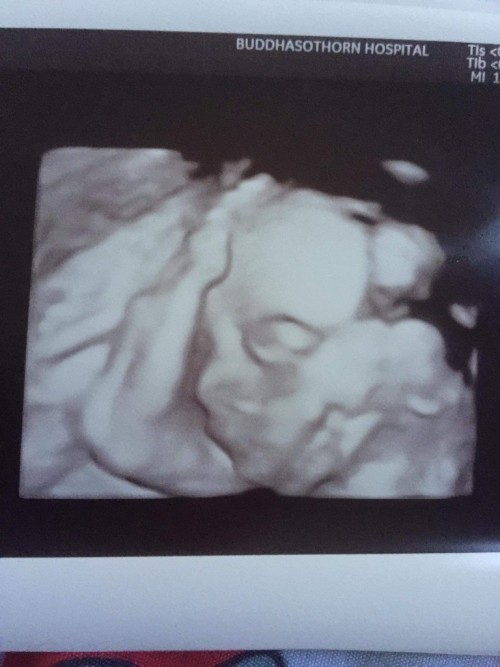

บ้านหน้าอ้วนมากเลย ท้อง2ค่ะ ซาว4มิติ